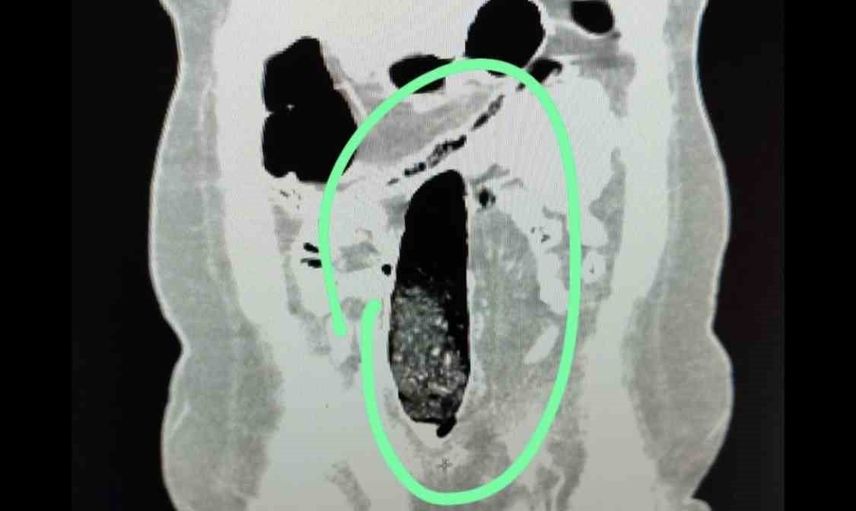

Yapılan kontrollerde şüpheli şahısların iç beden muayeneleri gerçekleştirilmiş; şahısların vücutlarının doğal boşlukları ve bağırsaklarında uyuşturucu madde bulunduğu belirlenmiştir. Tıbbi müdahale ile söz konusu maddelerin çıkarılması sağlanmıştır.

Tıbbi müdahale sonucu, F.V. isimli kadın şahıstan üç parça halinde toplam 397,78 gram metamfetamin ele geçirilmiş; S.İ. isimli erkek şahıstan ise 24 adet sentetik hap ile üç parça halinde toplam 167,68 gram metamfetamin elde edilmiştir.